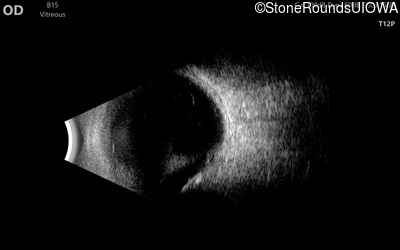

B-Scan Ultrasonography - Right - 20/200 sc

Exemplar